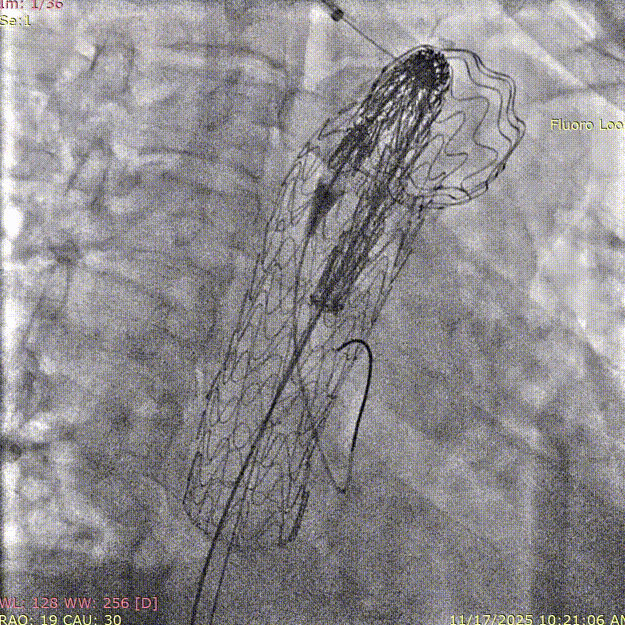

3. 右侧肱动脉置入斑马导丝,建立右肱动脉与股动脉之间工作轨道,沿加硬导丝及斑马导丝置入TBE主体支架(型号:TAC123715W)。调整机头角度,确认双导丝间无缠绕。

斑马导丝是治疗什么的「胸有乾坤」至简至易 行之有效—— Zone 0 TBE植入治疗弓部动脉瘤病例报道_https://www.jmylbn.com_新闻资讯_第16张

斑马导丝是治疗什么的「胸有乾坤」至简至易 行之有效—— Zone 0 TBE植入治疗弓部动脉瘤病例报道_https://www.jmylbn.com_新闻资讯_第17张